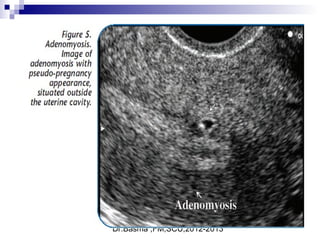

True gestational sacTrue gestational sac must bemust be differentiated fromdifferentiated from

pseudo sacpseudo sac

 Embryonic Vesicle (Primary yolk sac

 Round or oval.

 Double ring )Ring of decidualized

endometrium.

 Fundal or mid-portion of the uterus.

 May occasionally implant low down in the

uterine cavity.